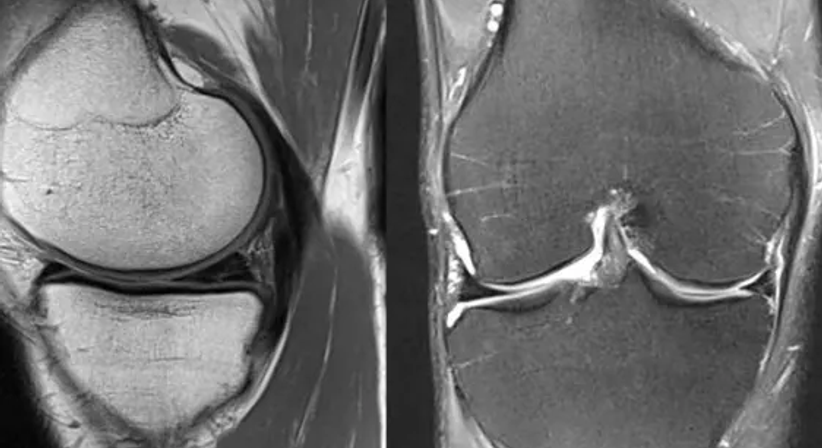

Die Arthroskopie wird für Diagnose und Therapie eingesetzt und findet am häufigsten bei Meniskus- und Knorpelschäden am Kniegelenk ihren Einsatz. Die Gelenkspiegelung erfolgt mithilfe eines sogenannten Arthroskops, das über einen kleinen Hautschnitt in das Gelenk eingeführt wird. Dadurch kann das Innere des Gelenks in Echtzeit untersucht und gegebenenfalls chirurgisch therapiert werden.

Liegt ein Meniskusriss vor, wird dieser, je nach Rissart, Begleitpathologien und Alter des Patienten, entfernt oder genäht. Im Falle von Knorpelschäden kann mitunter mittels Mikrofrakturierung eine Verbesserung der Knorpelregeneration erreicht werden.